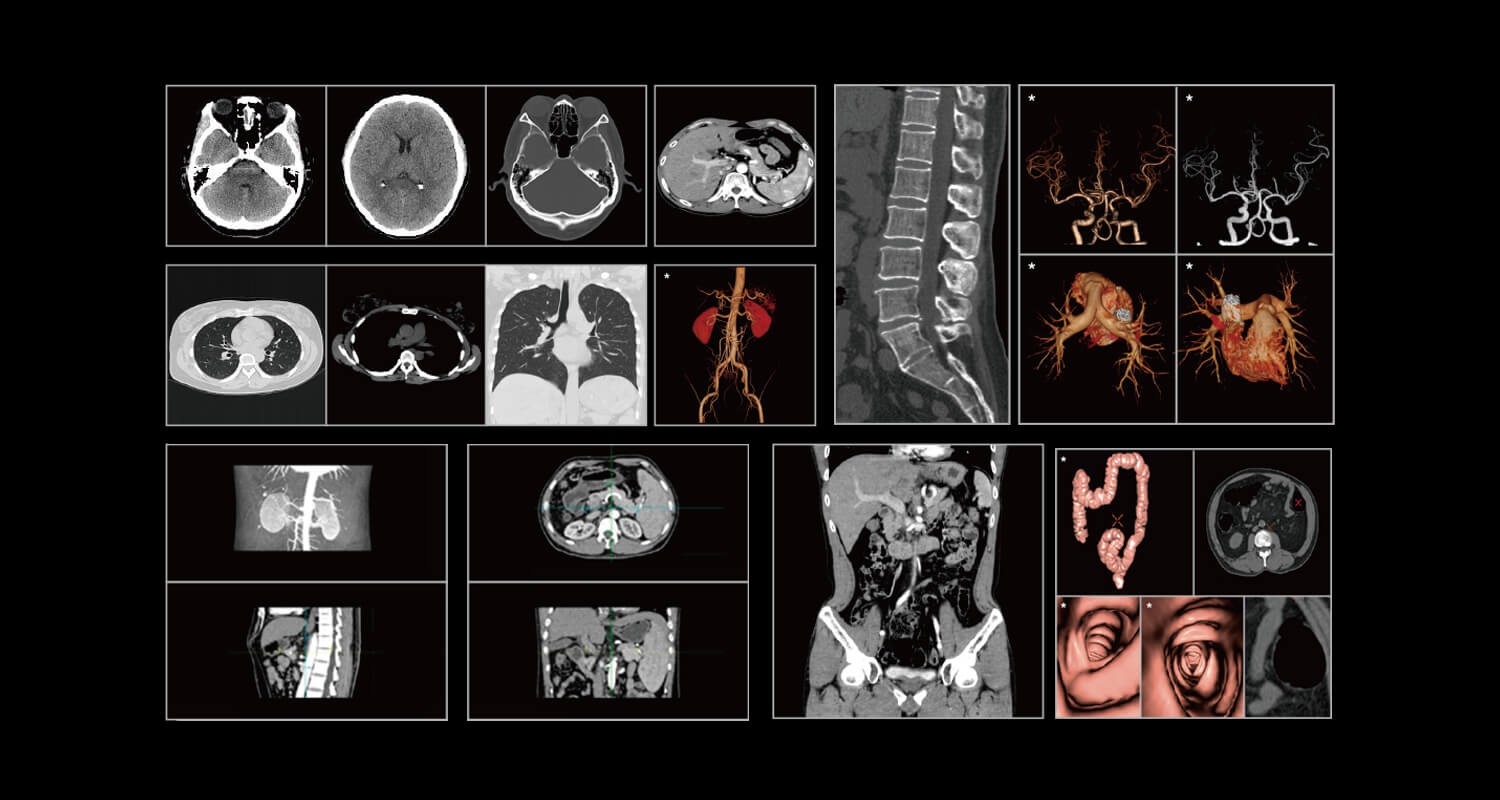

Clinical Gallery